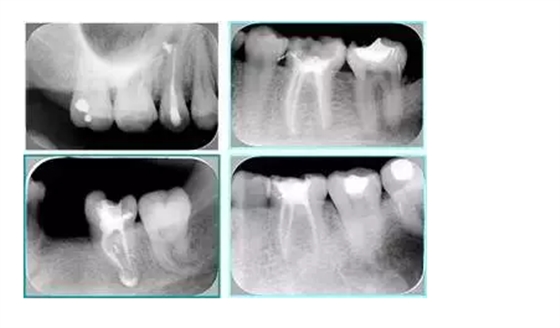

常見不良根管充填物有干髓、塑化、塑化 + 根充和不良根充。

( 1 )干髓。

干髓治療時(shí),開髓后髓腔里注入甲醛甲酚 FC 灌髓,三聚甲醛固定,髓室底放置三聚甲醛緩慢釋放,進(jìn)行根管無害化處理。髓腔緩慢壞死,機(jī)體代償出現(xiàn)根管鈣化。如果患者在封閉腔出現(xiàn)出現(xiàn)病變,由于髓腔鈣化,根管堵塞嚴(yán)重,檢查治療比較困難。

左圖和上圖為干髓治療后牙齒,齲齒疏通后進(jìn)行根管充填。

( 2 )塑化。

傳統(tǒng)的治療思維:塑化治療后患者需將塑化液清理干凈,達(dá)到徹底根管治療目的。

目前的治療思維:以前塑化治療效果好時(shí)不必清理干凈塑化液。對于根尖沒有病變的患者,可借助溶解劑建立通路;根尖存在病變的患者往往是塑化治療不理想患者,需要徹底打通通路。

( 3 )塑化 + 根充。

如圖為塑化加根充處理后牙齒 X 線片。

( 4 )不良根充。

不良填充與操作有關(guān),采用輔助放大設(shè)備可有效預(yù)防不良填充.解決方法:

6. 鈣化

常見有修復(fù)性鈣化和增齡性鈣化。下面為根管鈣化 X 線片。